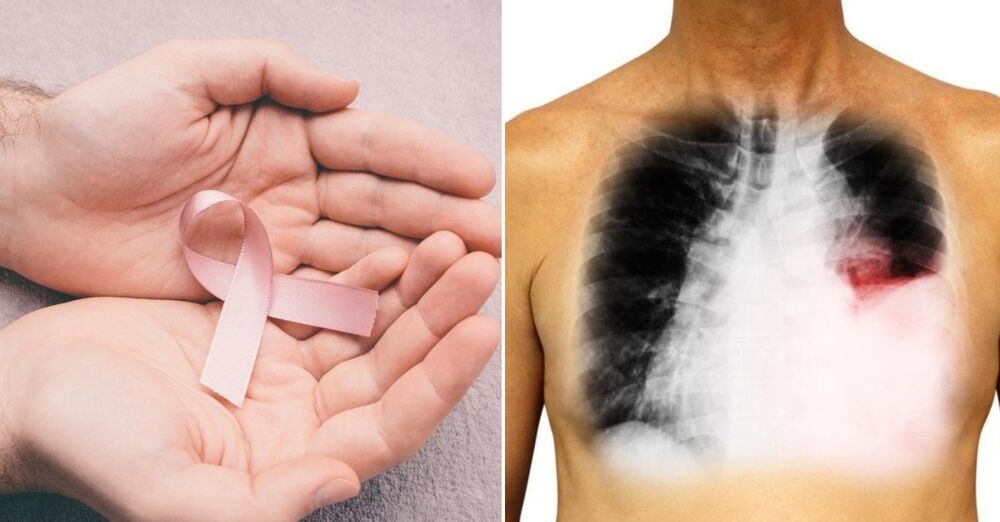

Zbog toga je i statistika u vezi sa obolelima od raka pluća u našoj zemlji - poražavajuća. Svake godine u našoj zemlji od karcinoma pluća oboli 6.500 ljudi, a umre njih 4.600.

- Rak pluća javlja se u najvećoj meri posle pedesete godine života. Cigarete su ključni faktor rizika za nastanak bolesti. U poslednjih deset godina svega devet odsto obolelih od raka pluća su bili nepušači. Međutim, u okviru skrininga kroz koji je do sada prošlo 1.200 osoba, svega četiri odsto pušača kazalo je da se brine da će oboleti od kancera. Kod nas je pušenje široko rasporostranjeno i društveno prihvatljivo. Cilj nam je uvođenje nacionalnog skrininga - rekla je dr Bojanić

- Još je strašniji podatak da je tokom prethodne decenije čak 55 odsto više žena među obolelima. Ova bolest nažalost nema nikakve simptome u ranoj fazi, brzo se razvija i brzo daje metastaze. Skener pluća otkriva bolest, jer rendgen ne može da locira promene i senke koje su manje od jednog centimetra. To znači da rendgen pokaže senku neke dve godine od nastanka bolesti, a to je već kasno. Skener bolest otkriva odmah, i najmanju promenu - objasnila je dr Snežana Bojanić.